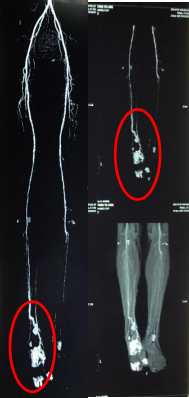

经与患者沟通,患者仍然存有对足部功能、美观程度及保肢愿望有较强烈的意愿。但该患者下肢CTA显示:患肢远端血管达中重度狭窄,前足血运完全中断。对现有的治疗技术提出了巨大的挑战。

通过周密的术前计划、精细的手术操作,精心的术后护理,患者术后第3天,即感到患肢末梢感觉有所恢复,经过骨科医护人员近1个月的精心照料,患者创面感染完全控制,肉芽生长活跃,复查CTA可见患肢前中足新生血管,最终创面完全愈合。术后2个月,创面愈合良好,色素沉着减轻。术后6个月随访,搬运骨块顺利愈合,无新发溃疡,足底支撑功能得以最大程度保留,患者满意度极高。